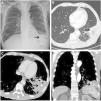

We report the case of a 72-year-old man with oropharyngeal squamous carcinoma treated with chemoradiotherapy, who had a nasogastric tube (NGT) placed due to dysphagia associated with mucositis. After accidental displacement, the NGT was repositioned in the emergency department. The patient presented 24h later with a complaint of dyspnea and left chest pain. The chest X-ray showed the distal tip of the NGT in the left lower lobe (Fig. 1A). The suggested diagnosis was chemical pneumonitis, intravenous antibiotic therapy was started, and he was admitted. During his stay, the chest computed tomography (CT) showed an image suggestive of resolving necrotizing pneumonia (Fig. 1B) and he was discharged with oral antibiotic therapy.

(A) Chest X-ray showing the nasogastric tube (NGT) with distal tip (arrow) in the left lower lung and alveolar infiltrate. (B) Chest CT of the left lower lung showing an area of hypodense consolidation containing air bubbles (arrow) suggestive of necrotizing pneumonia. (C, D) Axial and coronal slices, respectively, of the chest CT showing image of cavitary consolidation in left lower lung (arrow) containing active bleeding.

The patient presented 2 months later with life-threatening hemoptysis. CT angiography showed increased cavitary consolidation and an image of active bleeding: segmental pulmonary artery pseudoaneurysm could not be ruled out (Fig. 1C, D). Left lower lobectomy was performed and he was discharged 3 days later.